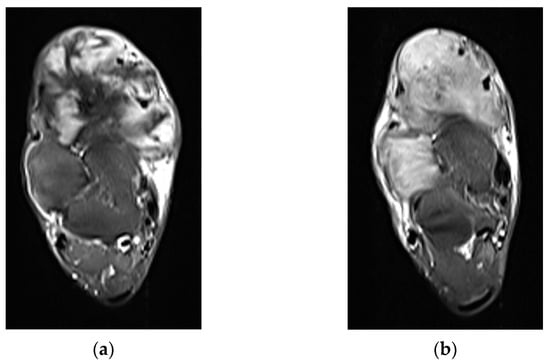

Depending on the location of the DT, additional secondary signs may be present. In extra-abdominal DTs, extension to adjacent subcutaneous fat or muscle can proceed along multiple fibrous bands, producing a “staghorn” appearance (”staghorn sign”), or along a muscle fiber or aponeurosis, creating a linear extension termed the “fascial tail sign” analogous to the “dural tail sign” seen with meningiomas [13]. DT can be found purely within or spanning multiple levels from the subcutaneous, muscular, and fascial layers. Superficial and deep intermuscular tumors with prominent fascial infiltration have a higher likelihood of treatment failure and postoperative recurrence than those within muscle [14,15]. For intermuscular DTs, there may be a thin rim of surrounding fat with feathery/flamelike margins (“flame sign”). In contrast, intraabdominal DTs, which are commonly located in the mesentery, often display a whorled appearance with ill-defined margins, representing a spiculated pattern of extension into the adjacent mesenteric fat. The irregular shapes and infiltrative margins displayed by DTs contribute to the difficulty in reliably measuring them in both 3D and single plane techniques (Figure 1). While the correlation is not perfect, the percentage of tumor volume that is T2 hyperintense likely has prognostic importance in predicting tumors that are at risk for progression with observation only [16,17]. One retrospective study of 37 patients managed with observation showing that ≥90% volume of T2 hyperintensity is associated with 1-year PFS of only 55% (n = 20), compared with 94% in the <90% group (n = 17) [17].

Figure 1.

Morphologic features of DTs that can be challenging to accurately measure on T2-weighted MR, including (a) infiltrative margins in a DT above the shoulder joint (arrows), (b) “fascial tail” extension along the popliteus muscle in this patient with DT of the left calf musculature (arrows), and (c) elongated, plaque-like morphology extending along the superficial gastrocnemius (arrowheads).